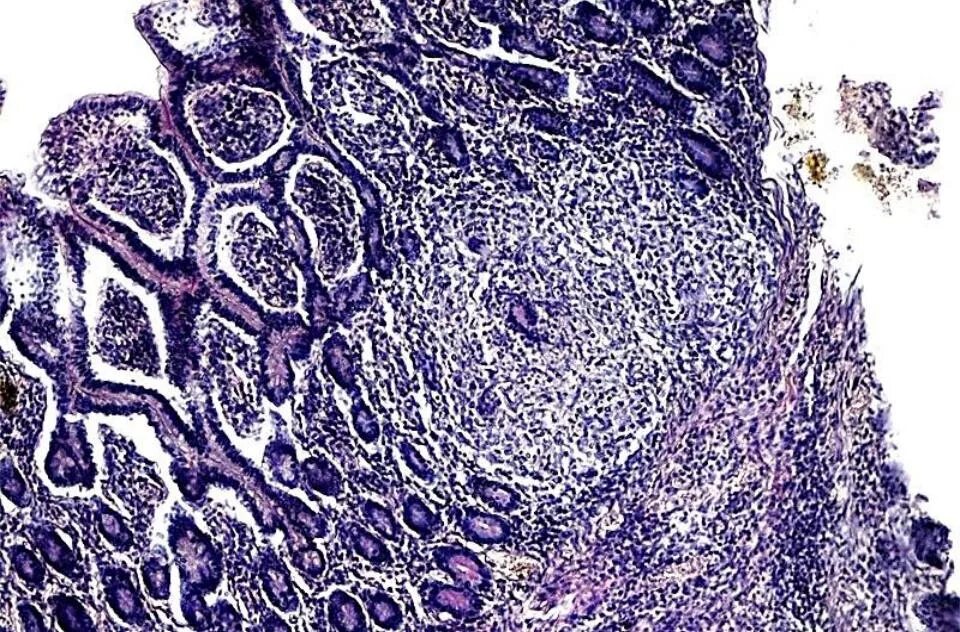

Гистологические заболевания